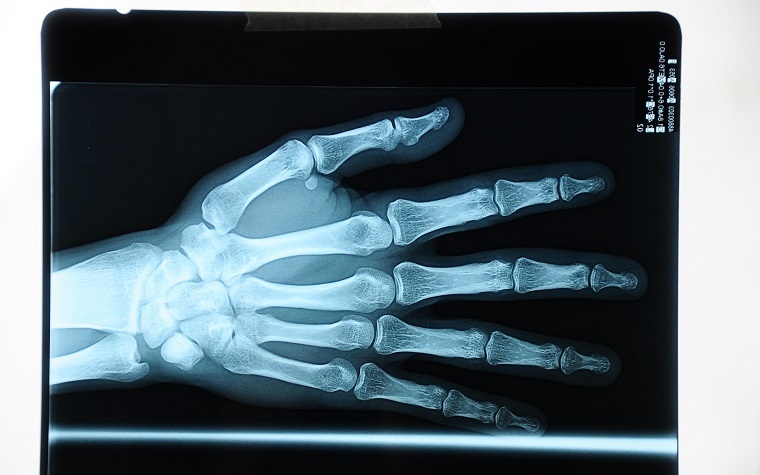

The American Academy of Family Physicians (AAFP) said it endorses the new osteoporosis treatment guidelines issued by the American College of Physicians (ACP).

The new guidelines, which include a clinical practice guideline, recommend that women with osteoporosis be treated with biphosphonates. Common drug names of bisphosphonates include Fosamax, Actonel, and Atelvia. Other recommended pharmaceutical treatments include Prolia and Reclast.

The ACP also recommends that physicians abandon the practice of bone density monitoring during the five-year recommended treatment period in women, concluding that current scientific evidence shows no benefit for the practice.

The ACP guideline is consistent with the AAFP guidelines for osteoporosis screening, recommending that women 65 and older be screened for the condition, as well as those with increased risk factors at a younger age.